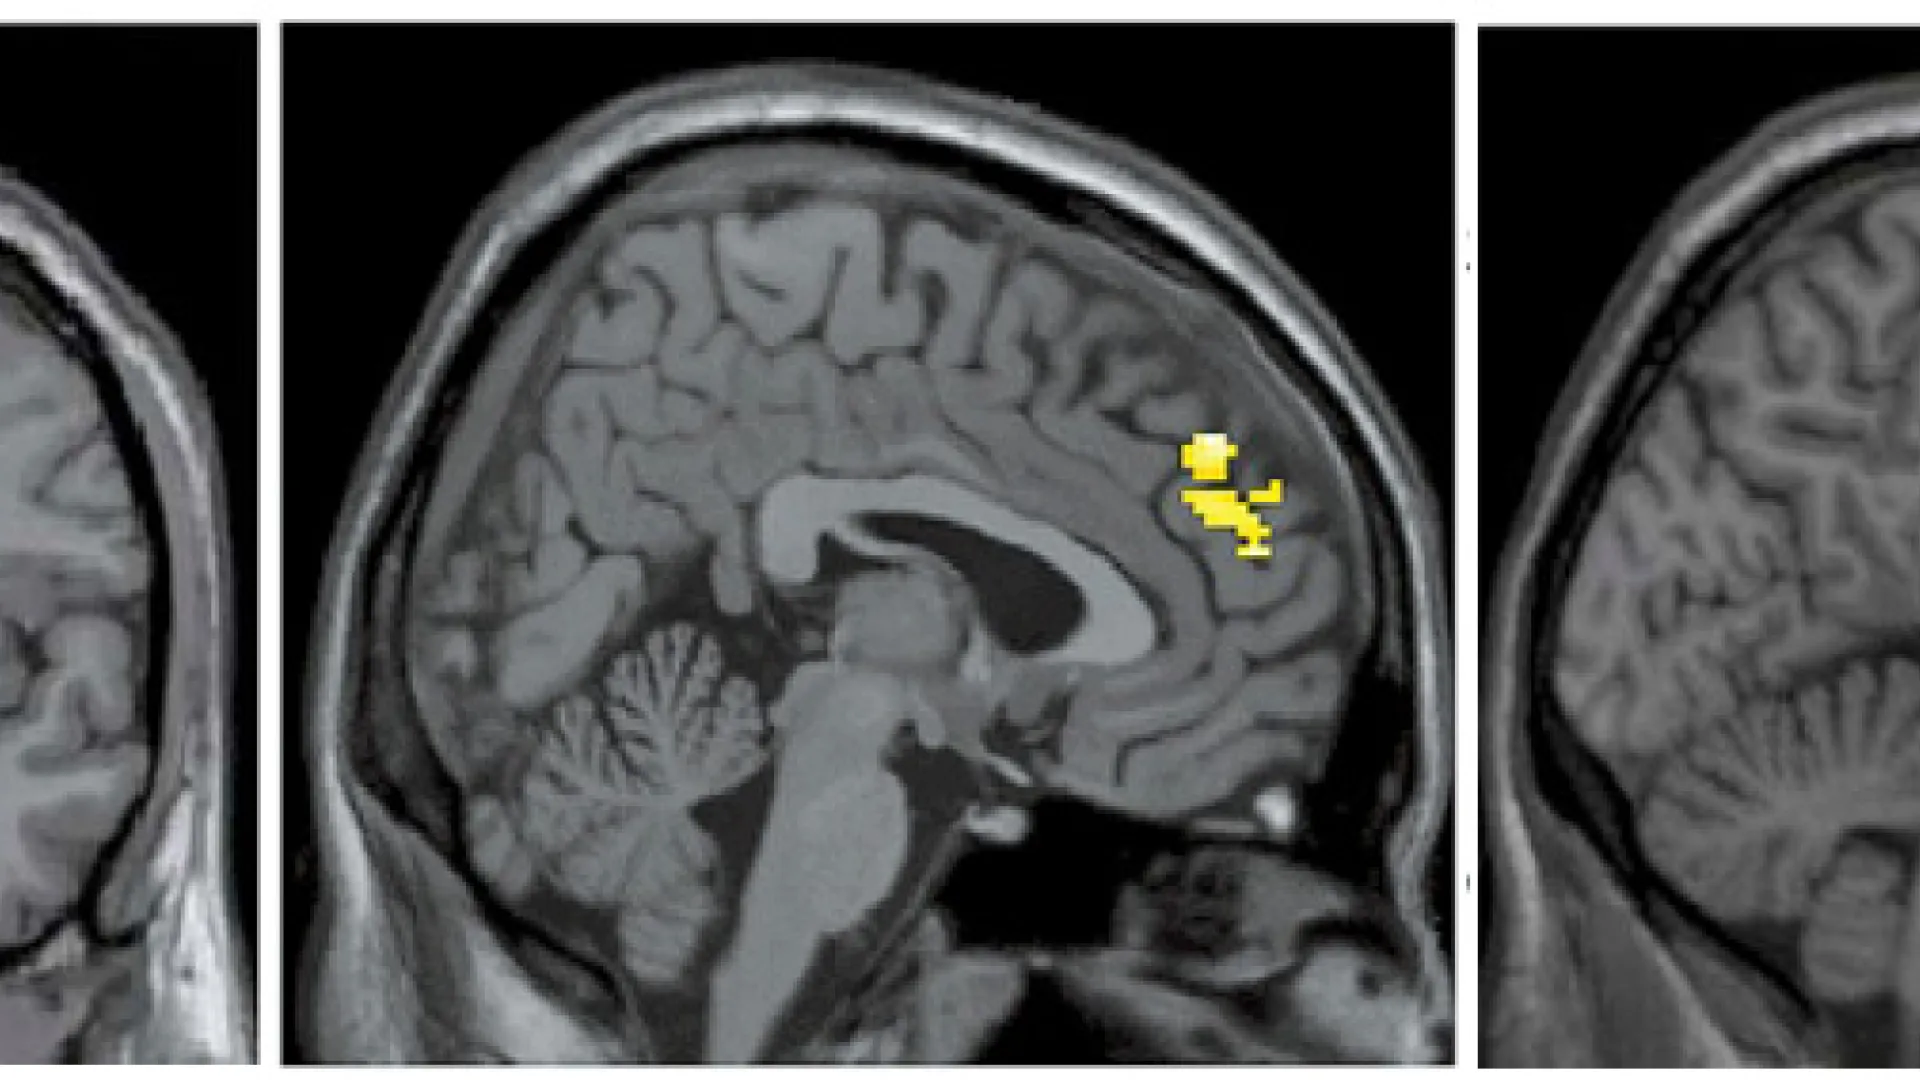

Brain images show the differences in activity patterns between the two groups of subjects that professor of psychology Jill Hooley examined. The brains of recovered depressed subjects (left) had more active amygdalae while listening to criticism than did the brains of subjects who had never been depressed. The brains of the latter showed more activation in the dorsolateral prefrontal cortex (center) and the anterior cingulate cortex (right) compared to brains of subjects with a history of depression.

In the images that resulted, the researchers could see that the brains of the formerly depressed subjects processed the critical comments in a markedly different way than the brains of the subjects who’d never been clinically depressed. The images highlighted three brain areas that seem to work together to regulate emotional responses and which had been flagged in previous research as areas of interest to the study of depression. As the formerly depressed subjects listened to the criticism, they showed significantly less activity, compared to the control group, in the dorsolateral prefrontal cortex, a late-developing area involved in planning and working memory, and in the anterior cingulate cortex, which lies deeper in the brain (wrapped around the corpus callosum that connects the two hemispheres) and is involved with a wide variety of functions including assessing the motivational and emotional content of stimuli; response selection; and problem-solving. Instead, their brains showed increased activity in the amygdalae, which lie deeper still in the brain and form part of the limbic system.

What seems to be happening, says Hooley, is that criticism activates the amygdalae in the brains of those who have been depressed, perhaps tripping a primal emotional response and bypassing the more analytical response seen in the brains of subjects with no history of depression. Yet when asked about their mood as they listened to the critical remarks, the formerly depressed subjects didn’t report feeling worse than the control group. They had exhibited no symptoms at all for some time (six months as a minimum to qualify for inclusion, and 20 months on average); they acted normally and felt normal. But their brains told a different story and, says Hooley, “They had no idea this was happening.”